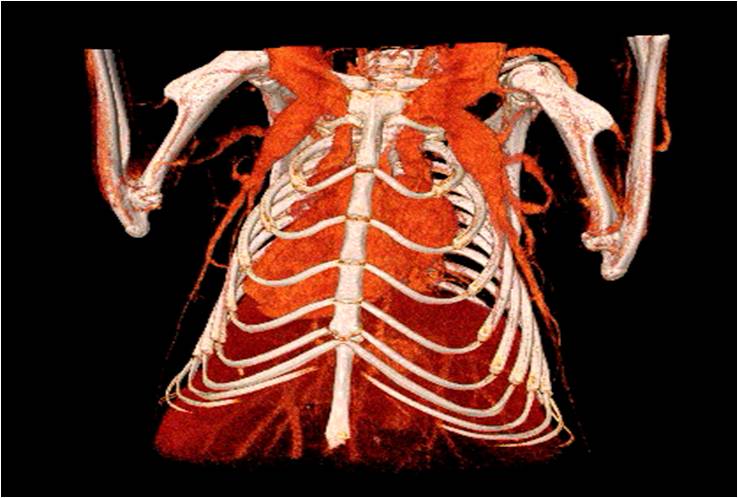

心血管

胸部和心血管的層析成像 胸部和心血管的3D圖像

心血管.jpg 心血管1.jpg